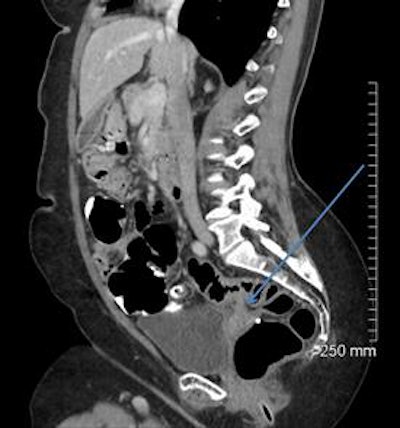

A 68-year-old woman with a fistula, categorized as C1D4E2, between the diverticular sigmoid and the vaginal vault. All images courtesy of Dr. John Hanson.

A 52-year-old man with a benign stricture, categorized as C4E1D4. The arrows highlight the smooth gradual transmural thickening within a diverticular laden sigmoid colon. Benign stricture was confirmed with surgical resection.